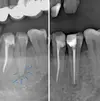

Implant treatment